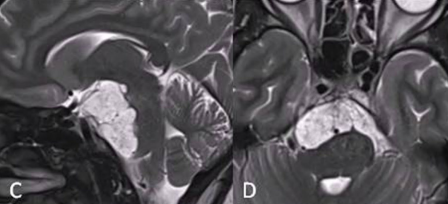

在Ⅰ期手术中,福教授采用内镜经鼻入路切除肿瘤的硬膜外部分,成功移除了斜坡和海绵窦区域的肿瘤,这样做能够减少脑脊液泄漏和神经血管损伤的风险。活检结果也证实了是典型的脊索瘤。针对硬膜内部分的肿瘤,则需要等待Ⅱ期手术再进行广泛切除。

两个月后,潇潇的身体恢复良好,于是,福教授又为她进行了Ⅱ期手术。这一次采取的是右侧的mini经岩骨入路,最终实现全切,且无任何新发神经功能缺损。

然而,对于狡猾的脊索瘤而言,全切相当于为整体的治疗开了一个好头,后续仍然要进行辅助治疗,才能最大程度延缓复发。于是,在福教授的建议下,潇潇开始接受质子束治疗(PBT)。在5个月的随访期间,潇潇并未出现不适,神经系统检查结果十分正常,而且头面部的美观效果也非常好,这也得益于福教授所采取的两个微创入路。